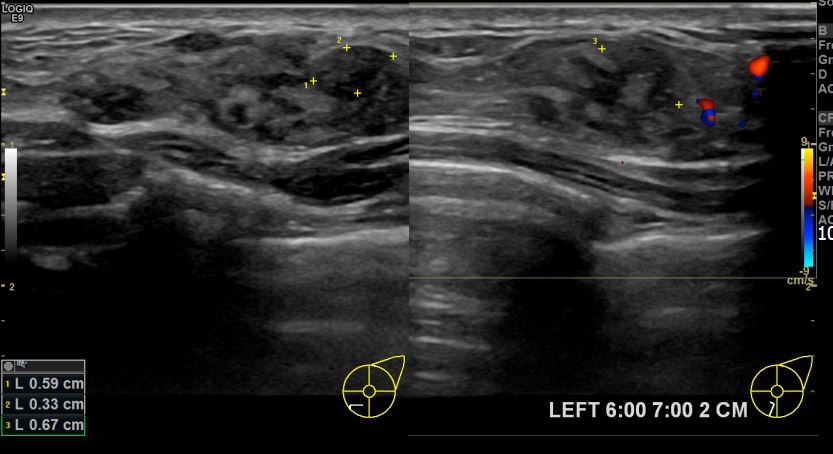

아산유외과개원후 702번째 유방암진단

상기환자 좌측유방에 딱딱한 멍울이만져져 내원하신 30대여성분으로 좌측유방의 혹 조직검사시행후 유방암 진단되었습니다.